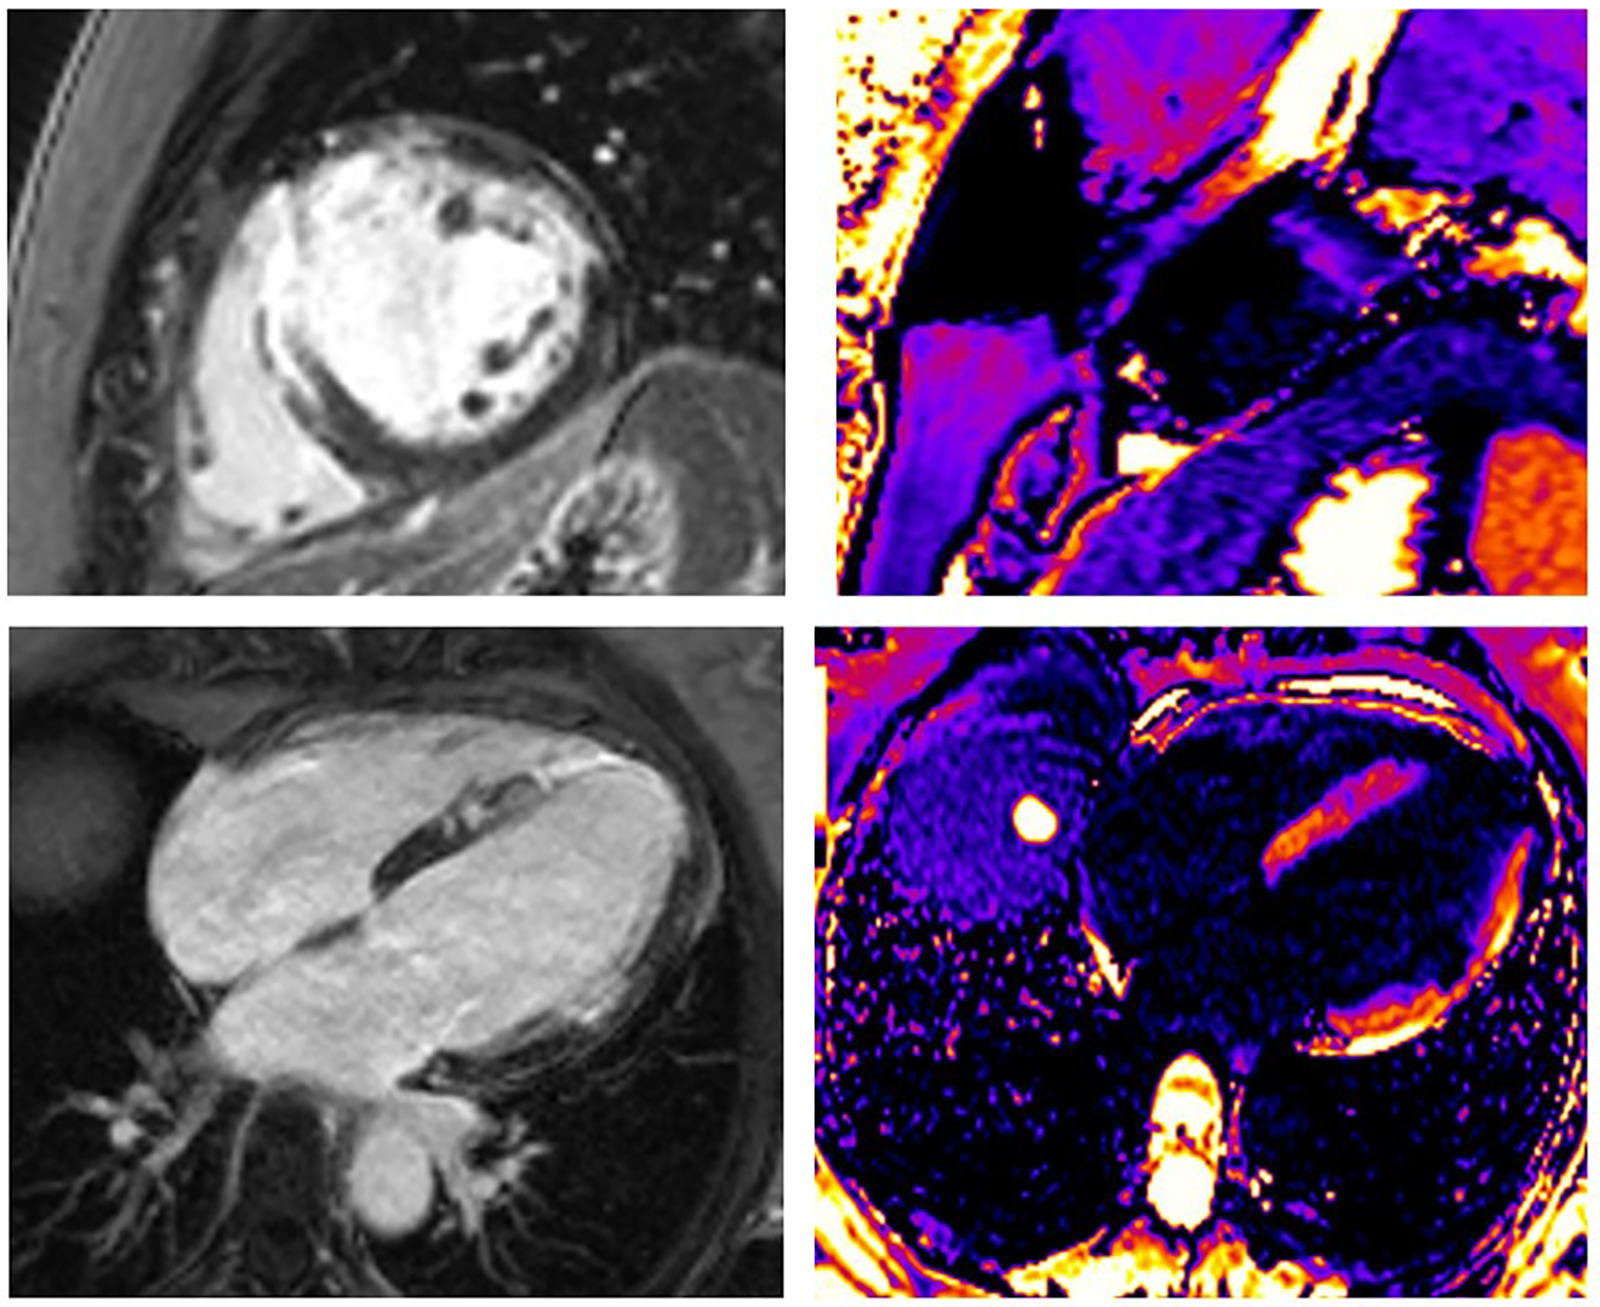

The occurrence of myocardial injury in SCAD, which presents as myocardial infarction, may not always be visible and depends on the type of SCAD. It is in accordance with thrombolysis in myocardial infarction (TIMI) flow and the speed of healing coronary disease. Figures 24 present three patients with different types of SCAD and myocardial infarct sizes, which depend on that.

FIGURE 3

www.frontiersin.org

Figure 3. A 43-year-old woman presented as STEMI anterior localization, SCAD on left anterior artery type 3, and TIMI flow 0, treated with percutaneous coronary intervention (PCI) and implanted four stents guided with intravascular ultrasound (IVUS). LGE was seen in the medio-apical part of the septum, apical parts of the anterior wall transmurally, and in the medial parts of the anterior wall in the sub-endocardial layer. Using post-contrast T1 mapping, the zone of fibrosis, which was the zone of infarction, was also present in the same segments. The size of fibrosis (infarct size) was 17%.

FIGURE 4

Figure 4. A 55-year-old woman presented STEMI anterior localization, SCAD on left anterior artery type 2A, and TIMI flow 2, treated with conservative medical therapy. There was no LGE in the myocardium of LV. Using post-contrast T1 mapping, the values were normal. The infarct size was 0%.